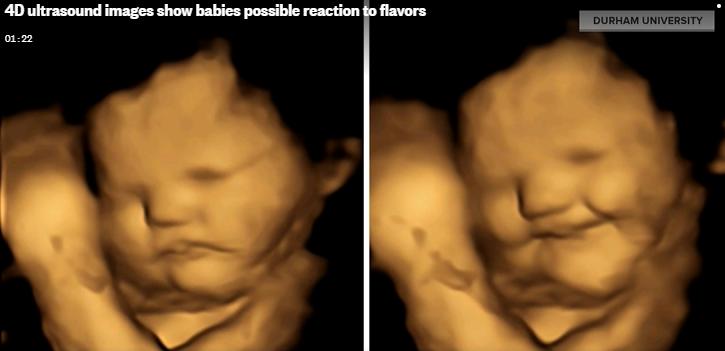

英國最新研究發現,胎兒仍在母腹時已會對不同味道作出不同反應,當母親吃下胡蘿蔔時,胎兒會露出類似微笑的表情。 電視截圖

英國最新研究發現,胎兒仍在母腹時已會對不同味道作出不同反應,母親食用羽衣甘藍後,胎兒會因此嚐到苦味而皺眉頭,相反母親吃下胡蘿蔔時,胎兒會露出類似微笑的表情。這次是科學家首次研究胎兒對味覺刺激的反應,相信其結果有助改善兒童偏食的習慣。